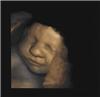

Las expresiones faciales se desarrollan antes de nacer 15/09/2011

En el vientre materno, los bebés desarrollan una gama de expresiones faciales identificables, como las de la risa o el llanto. Por primera vez, un grupo de investigadores de las universidades británicas de Durham y de Lancaster ha podido captar dichas expresiones reconocibles en bebés aún no nacidos, entre las semanas 24 y 36 de su gestación. Es en ese periodo en el que los movimientos faciales de los pequeños se vuelven más complejos, explican los científicos. El registro de imágenes se realizó en repetidas ocasiones, con escáneres de ultrasonido. De esta forma, se pudo comprobar que los movimientos de la cara de los fetos iban variando con el tiempo. Así, a las 24 semanas de gestación, los pequeños eran capaces de mover un músculo de su cara cada vez (por ejemplo, estirar los labios o abrir su boca). Pero más adelante, a las 35 semanas de gestación, ya eran capaces de combinar varios movimientos musculares del rostro, como expandir los labios, mover las cejas y hundir el surco nasolabial. Es decir, ya generaban expresiones faciales reconocibles y complejas. Según los investigadores, el descubrimiento aclara uno de los procesos del desarrollo fetal y demuestra que los bebés nacen ya con los movimientos faciales del llanto y la risa desarrollados. Por otro lado, este hallazgo podría ayudar a identificar problemas de salud de los fetos dentro del útero, dado que existe una relación entre los patrones de comportamiento fetales y el desarrollo del cerebro. La observación de diferencias entre un progreso anómalo de las expresiones faciales fetales y un progreso corriente podría indicar, por tanto, problemas en el desarrollo cerebral. En próximas investigaciones, los científicos analizarán si se puede determinar si las embarazadas fuman o no a partir de los movimientos faciales de sus fetos. Asimismo, examinarán el desarrollo de expresiones faciales fetales vinculadas a la ira, la sonrisa y la tristeza. Más información Nuevo comentario: